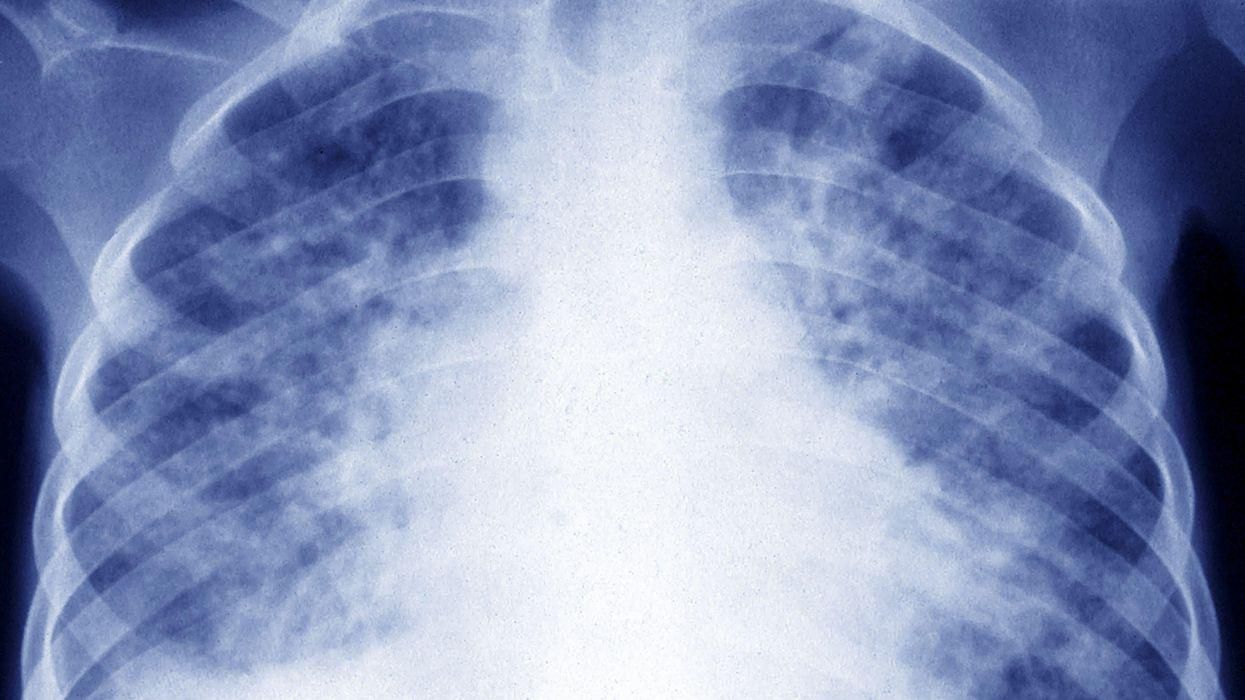

When she refused to receive an informal, over-the-phone diagnosis and pushed for an X-ray, her fears were confirmed: She had a cancerous mass inside her chest, measuring approximately four inches. She was soon diagnosed with Hodgkin's lymphoma.